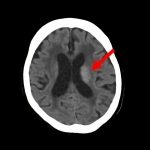

断層撮影

手術前2